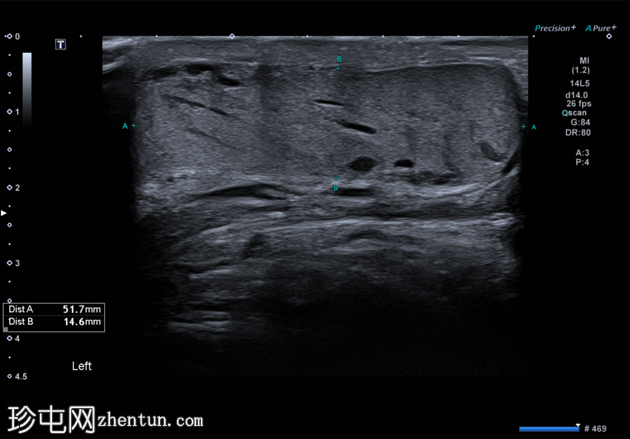

横切面

左侧睾丸内血管呈迂曲管状扩张,Valsalva动作可见充血。

典型的管状睾丸内精索静脉曲张超声表现,Valsalva动作可见扩张的睾丸内静脉充血。睾丸内精索静脉曲张常与同侧儿童时期睾丸固定术相关,本例患者即曾接受过该手术,且多见于左侧,本例亦属如此。